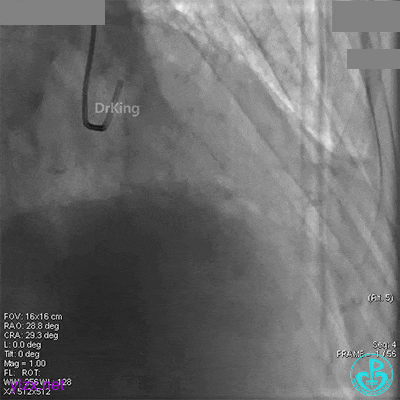

回旋支中段植入2.75×33mm支架后造影,前向血流中断,患者开始出现胸痛。

闭塞段植入2.75×33mm支架后前向血流中断,要排除无复流和支架两端夹层。